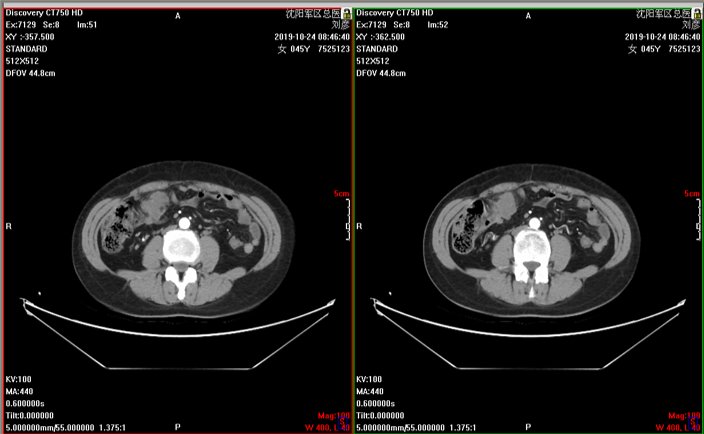

2019-10-24胸腹部CT:双肺未见异常,乙状结肠癌术后改变,腹腔、盆腔多发结节,考虑转移瘤,较前增多、增大。